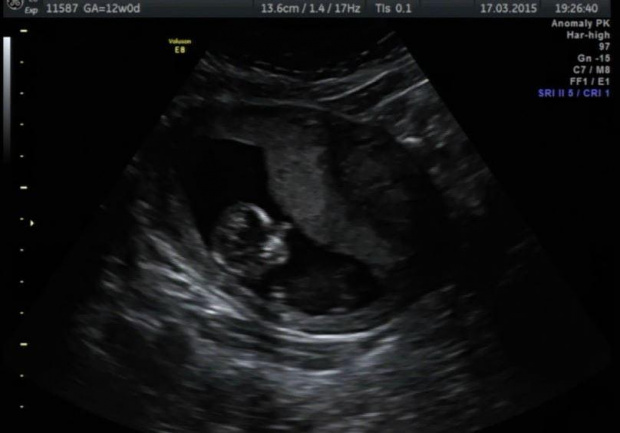

Dziewczyny jestem przeszczęśliwa

krwiak sie wchłonął. Jak to lekarz powiedzial mam pozwolenie na wizyty u znajomych, restauracje i inne komfortowe wyjścia. Żadnych sportów, zakupów i spacery tez raczej jeszcze nie ale i tak sie cieszę

Niestety mam też nisko lozysko, na szczęście na tylnej ścianie wiec powinno sie jeszcze podnieść!

Aaaa i bedzie chłopak. Widzialam siusiaka. Powiem Wam szczerze, ze my od zawsze mielismy wkręcona córkę ale wiadomo, ze sie cieszymy